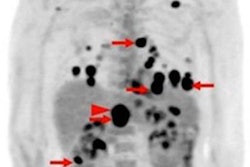

FDG-PET/CT scans can predict the success of radiation therapy in patients with spinal metastases, especially in regard to progression-free survival, according to a study published online September 28 in PLOS One.

All patients had FDG-PET/CT scans before and after treatment, with changes in metabolic responses measured by maximum, mean, and peak standardized uptake values (SUVmax, SUVmean, and SUVpeak), as well as metabolic tumor volume and total lesion glycolysis. Those variables were then correlated with the patients' clinical outcomes.